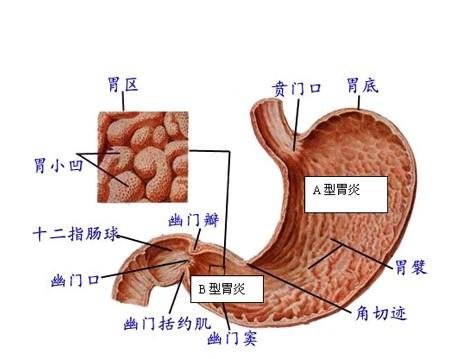

导读 萎缩性胃炎是胃黏膜呈慢性浅表性炎症的疾病,为消化系统常见病,属慢

导语 萎缩性胃炎也称慢性萎缩性胃炎,以胃黏膜上皮和腺体萎缩,数目减少,